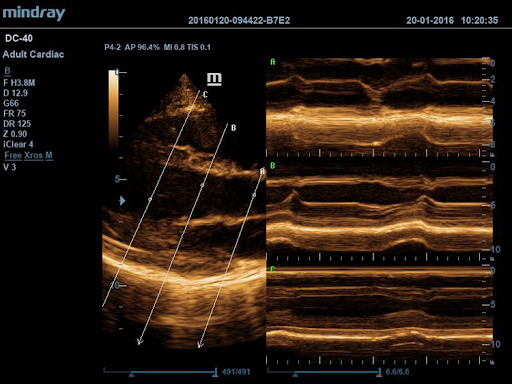

Free Xros M

Выполнение точных анатомических измерений с помощью свободно размещаемых линейных шаблонов позволяет достигать оптимального качества изображения за счет одновременного использования до 3 линейных шаблонов.

Free Xros CM

Позволяет получить полную информацию о движении сердечной мышцы в различных фазах сокращения и одновременно определять степень синхронизации миокарда. Точность результатов обеспечивается высокой частотой кадров.